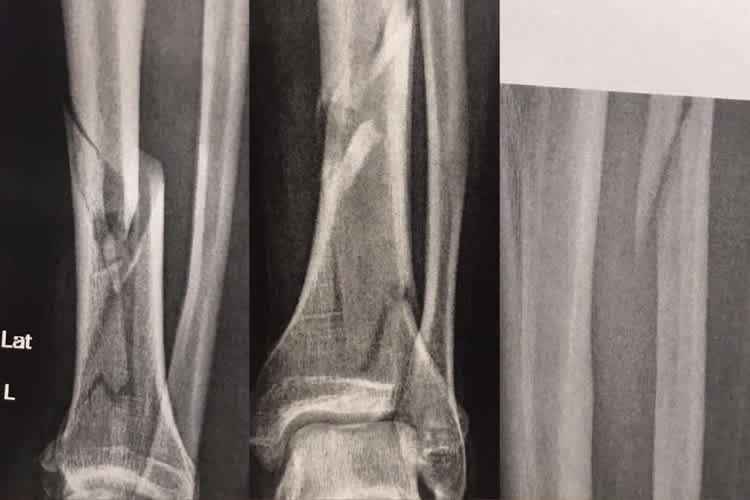

Doch sein Teamkollege Patryk Kosiniak, Sieger des Yamaha R6 Dunlop Cup 2016, kam im Freien Training von Assen gerade mal eine Runde weit. Sturz auf einer noch nicht ganz trockenen Stelle, Krankenhaus, Operation. Diagnose: Doppelter Unterschenkel-Bruch links. Die Saison dürfte damit gelaufen sein. Am Samstag-Abend erwischte es Sarah Heide vom Team Suzuki Laux. Zwar auf zwei Rädern, aber ohne Motor. Die IDM Superbike-Pilotin war mit dem Fahrrad unterwegs und stürzte unglücklich. Diagnose: rausgesprungene Kniescheibe. Zumindest die Rennen in Assen sind für Heide gestrichen. Damit fehlt eine der zwei Damen im Feld und es ist an Kawasaki-Pilotin Lucy Glöckner, die bei ihrem IDM-Comeback auf dem Schleizer Dreieck flott in die Top Ten gerauscht war, die Ehre der weiblichen IDM-Abteilung zu retten. Aus auch für Jessica Langstädtler vom Yamaha R6 Dunlop Cup. Sie verletzte sich bei einem Sturz im Training an der Schulter und übte sich anschliessend übers Strecken-Mikrofon als Co-Kommentatorin.